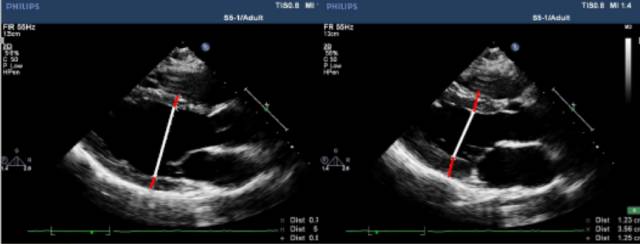

测量位置:胸骨旁左心室长轴,或二尖瓣瓣尖水平左心室短轴切面。

测量内容:室间隔厚度、左心室后壁厚度、左心室内径。

测量时相:收缩末期、舒张末期。

直接二维测量或在二维引导下的M-型曲线上测量。

图|胸骨旁左心长轴切面,二尖瓣瓣尖水平。左图为舒张末期,右图为收缩末期。

随着图像处理技术的改进,已经提高心脏结构的分辨率。可按照真实的组织和血流的界面来测量室间隔和左心室后壁的厚度,而不是像以前测量前缘回声之间的距离。